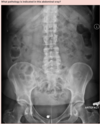

Answer: Ulcerative colitis

‘Lead pipe sign’ is noted in the descending colon, on the right border of this image.